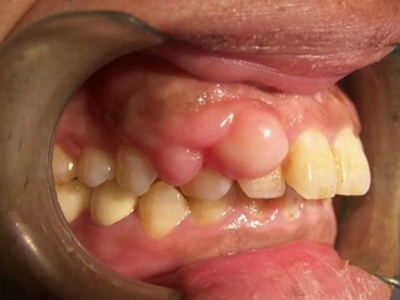

牙龈瘤是指发生在龈乳头部位的炎症反应性瘤样增生物,好发于女性,前磨牙区最为常见。牙龈瘤来源于牙周膜及牙龈的结缔组织,因其无肿瘤的生物学特征和结构,故非真性肿瘤,但切除后易复发,因此切除务必彻底,必要时拔除相关牙齿。

牙龈瘤多发于女性,以青年及中年人为常见,多发生于牙龈乳头部,位于唇、颊侧者较舌、腭侧者多,最常见的部位是前磨牙区。肿块较局限,呈圆形或椭圆形,有时呈分叶状,大小不一,直径由几毫米至数厘米。

肿块有的有蒂,如息肉状;有的无蒂,基底宽广,生长较慢,但在女性妊娠期间可能迅速增大。较大的肿块可以遮盖一部分牙及牙槽突,表面可见牙压痕,易被咬伤而发生溃疡,伴发感染。随着肿块的增长,牙槽骨壁逐渐被破坏,牙可能发生松动、移位。